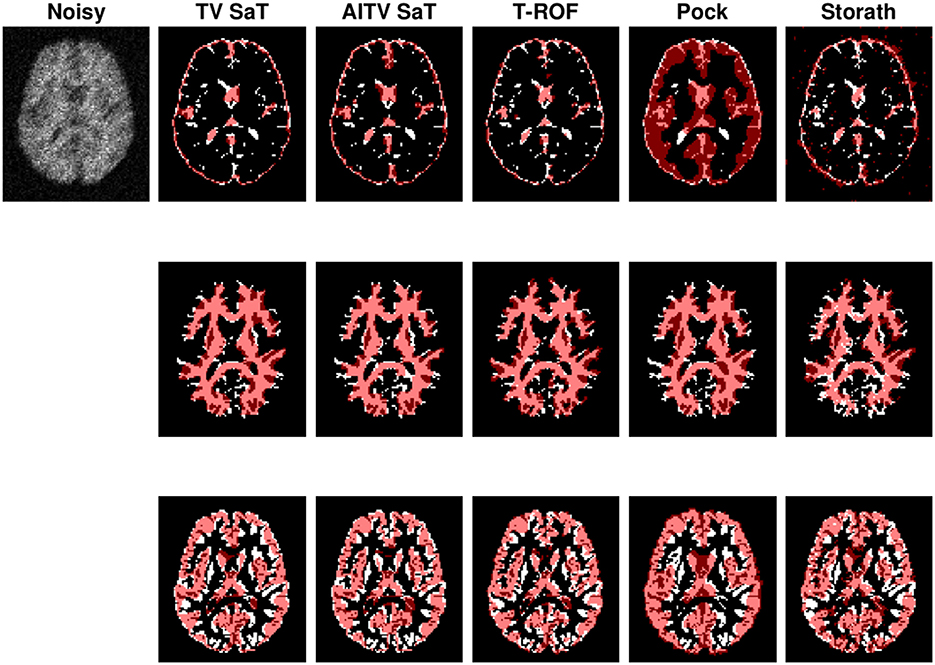

We examine the multiphase segmentation on the entire BrainWeb dataset (Aubert-Broche et al., 2006) that consists of 20 grayscale images as shown in Figure 3. Each image is of size 104 × 87 and has four regions to segment: background, cerebrospinal fluid (CSF), gray matter (GM), and white matter (WM). The pixel values are 10 (background), 48 (CSF), 106 (GM), and 154 (WM). The maximum intensity P = 154. We consider two cases: (1) P/2 no blur and (2) P/2 with motion blur specified by fspecial(“motion,” 5, 225). For the SaT methods, we have μ = 1.0, α = 0.6, 0.7, and λ = 4.0, 5.0 for case (1) and case (2), respectively.

Across all 20 images of the BrainWeb dataset, Table 2 reports the average DICE indices for CSF, GM, and WM and average computational times in seconds of the segmentation methods. For both cases (1) and (2), AITV SaT attains the highest average DICE indices for segmenting CSF, GM, and WM. AITV SaT is comparable to TV SaT and T-ROF in terms of computational time.

Figure 4 shows the segmentation results of the first image in Figure 3 for case (1). When segmenting CSF, the methods (TV SaT, AITV SaT, and Storath) yield similar visual results, while Pock fails to segment roughly half of the region. In addition, AITV SaT segments the most GM region with the least amount of noise artifacts than the other methods. Lastly, for WM segmentation, AITV SaT avoids the “holes” or “gaps” and segments fewer regions outside of the ground truth, thus outperforming TV SaT and Storath. For the three regions, T-ROF has the most noise artifacts in its segmentation results.

Figure 4. Segmentation result of the first image of Figure 3 with peak P/8 under Poisson noise with no blur. From top to bottom are segmentation results for CSF, GM, and WM.